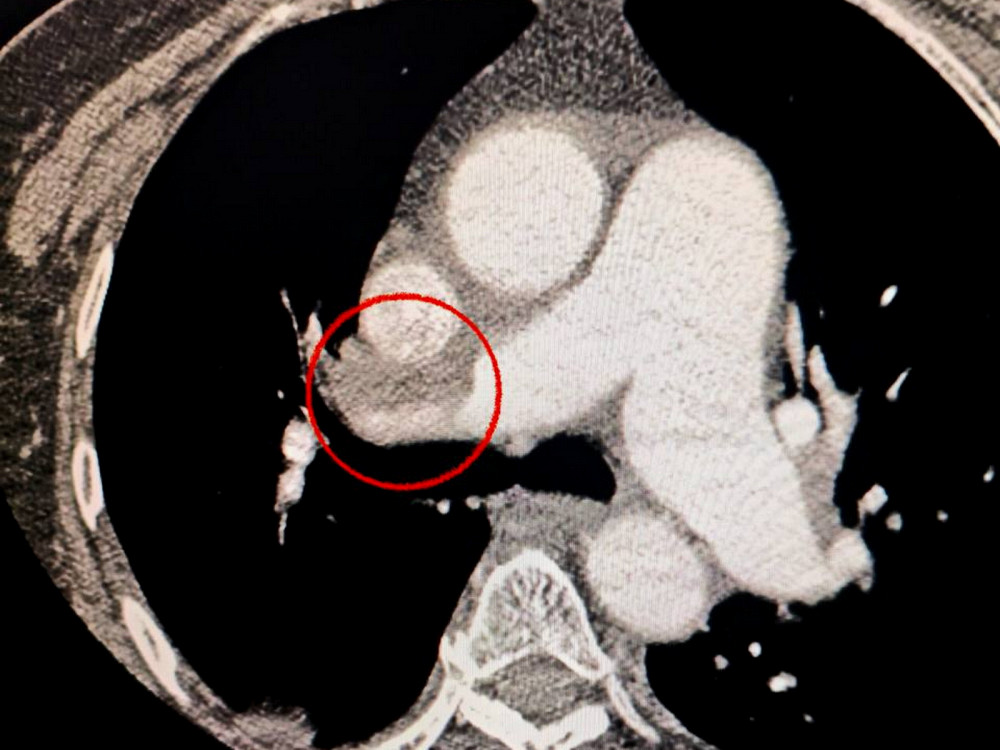

Пациентка, жительница Одессы, была госпитализирована с тяжелым случаем инсульта. Во время компьютерной томографии врачи обнаружили закрытие средней мозговой артерии.

Кроме того, специалисты отметили, что пациентке тяжело дышать, что привело к дополнительному обследованию легких. Диагноз усложнился из-за тромбоэмболии легочной артерии.